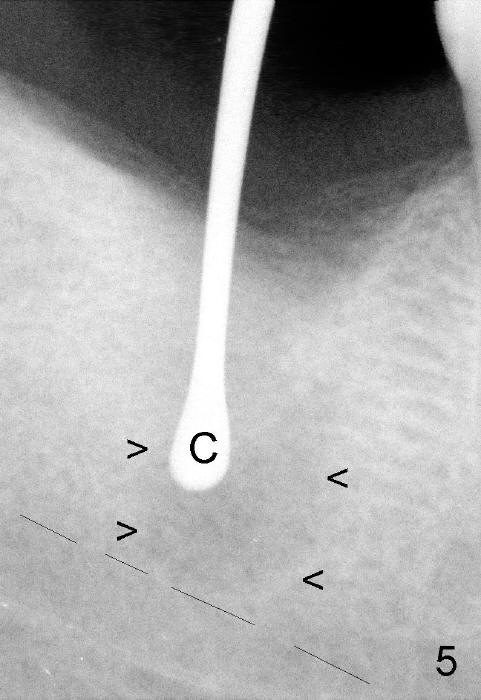

It is advantageous to place implant immediately or shortly (4-8 weeks) after extraction.  But most teeth to be extracted are potentially infected, such as in the case of Ms. Pei (Fig.1).  Periapical radiolucency (PARL) is not obvious prior to extraction. Six weeks post-extraction, osteotomy is finished with bone expansion and drilling (Fig.2 D, 5x14mm).  Tatum tapered implant is placed (Fig.3 I: 6x14). So far PARL is minimal if any (Fig.2,3 <).  Pain develops approximately 20 days post-implantation with expanding PARL (Fig.4 <).  Antibiotic treatment does not resolve the infection.  The implant has to be removed.  Infected granulation tissue is thoroughly removed from the apical portion of  the socket (Fig.5 <) with a curette (C).  Scaling and root planing is done for 4 quadrants.  A month later, potentially infected hard tissue is removed by reamers (Fig.6 D, 5 mm).  Bicon implant is buried inside the bone and separated from the oral cavity (Fig.7 I, 5x8).  At that time, there is a gap next to the implant (>).  Five months later, the gap disappears, suggesting implant osteointegration (Fig.8).  Extraoral cementation is done between abutment (A) and crown (C).  The abutment/crown unit is tapped into the implant with 2 visible threads (<).  The latter indicates that the abutment is completely seated.  Dashed lines in Fig.5-7 denote the upper border of the inferior alveolar canal.  PAs are taken 6 months (Fig.9) and 1 year 7 months (Fig.10) post cementation.  In all, it is a hassle to do re-implantation.  Efforts should be exerted to prevent post-implant infection.